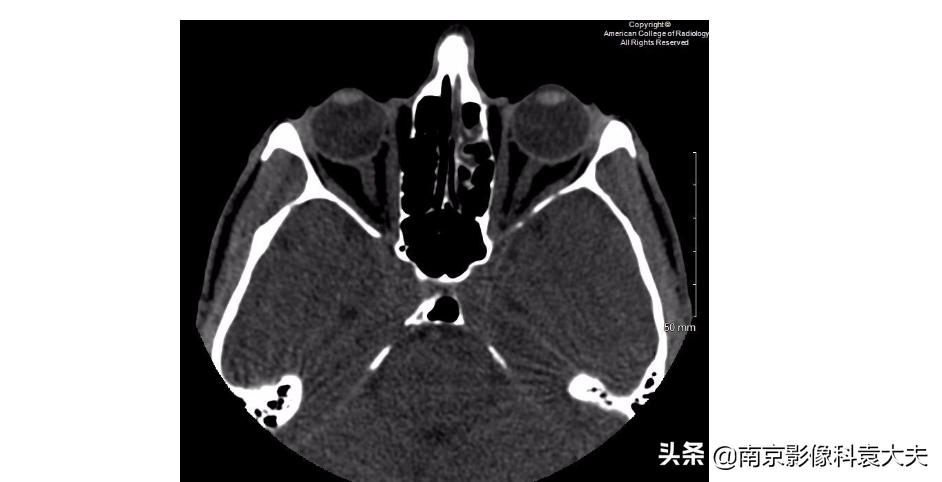

首先介绍一下病史:一位39岁男子在争吵后出现视力模糊。来医院急诊检查,医生开了CT平扫检查。

以下补充的眼眶CT图像显示有哪一种异常?

答案:BD

解释:

A:双侧眼球体是保持完整的。

B:右侧眼球外侧的高密度提示出血,这往往是眼外伤的直接征象。

C:没有钙化的眼内肿块不引起对视网膜母细胞瘤的考虑。视网膜母细胞瘤几乎全部是幼儿期的恶性肿瘤。

D:一个小的眼外异物位于右侧眼球的表面,它是患者角膜裂伤的一个潜在原因。

E:筛骨纸样板位于筛骨迷路(和眶内壁)的外侧面,而本例病人它是完整的。